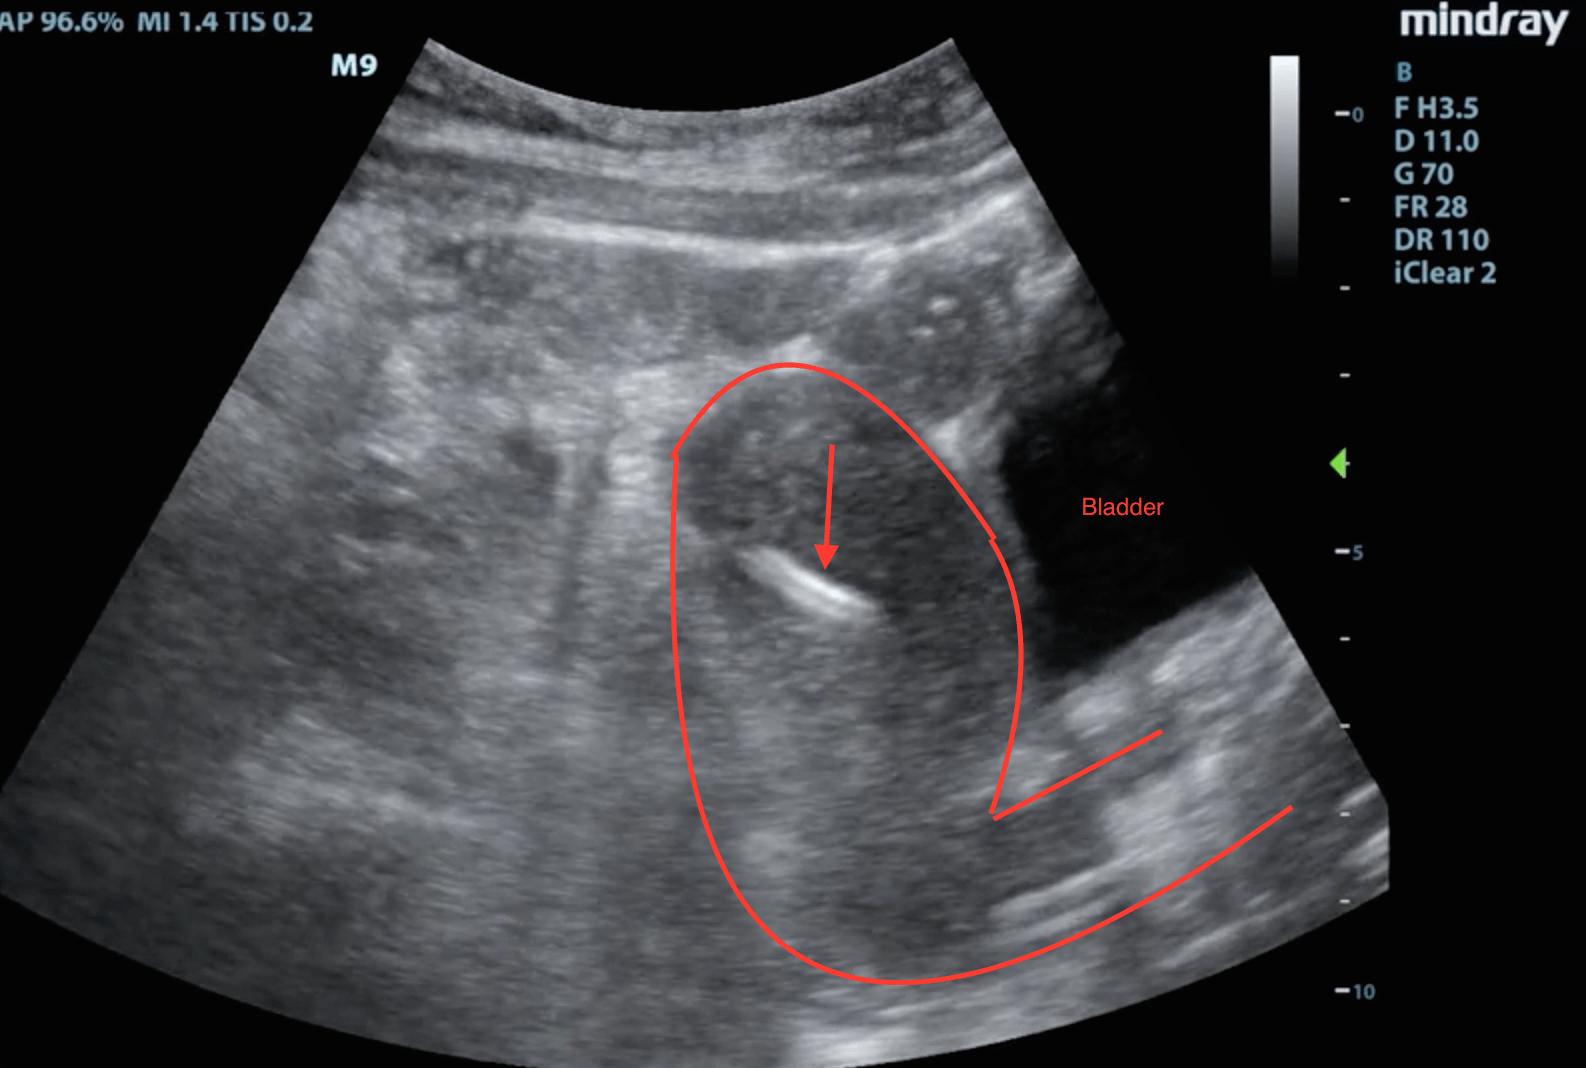

Here is a still shot of our patient:

The arrow is pointing to the IUD which clearly invades the myometrium.

The arrow in this picture is pointing to the endometrial stripe. The uterus and vaginal canal are outlined in red.